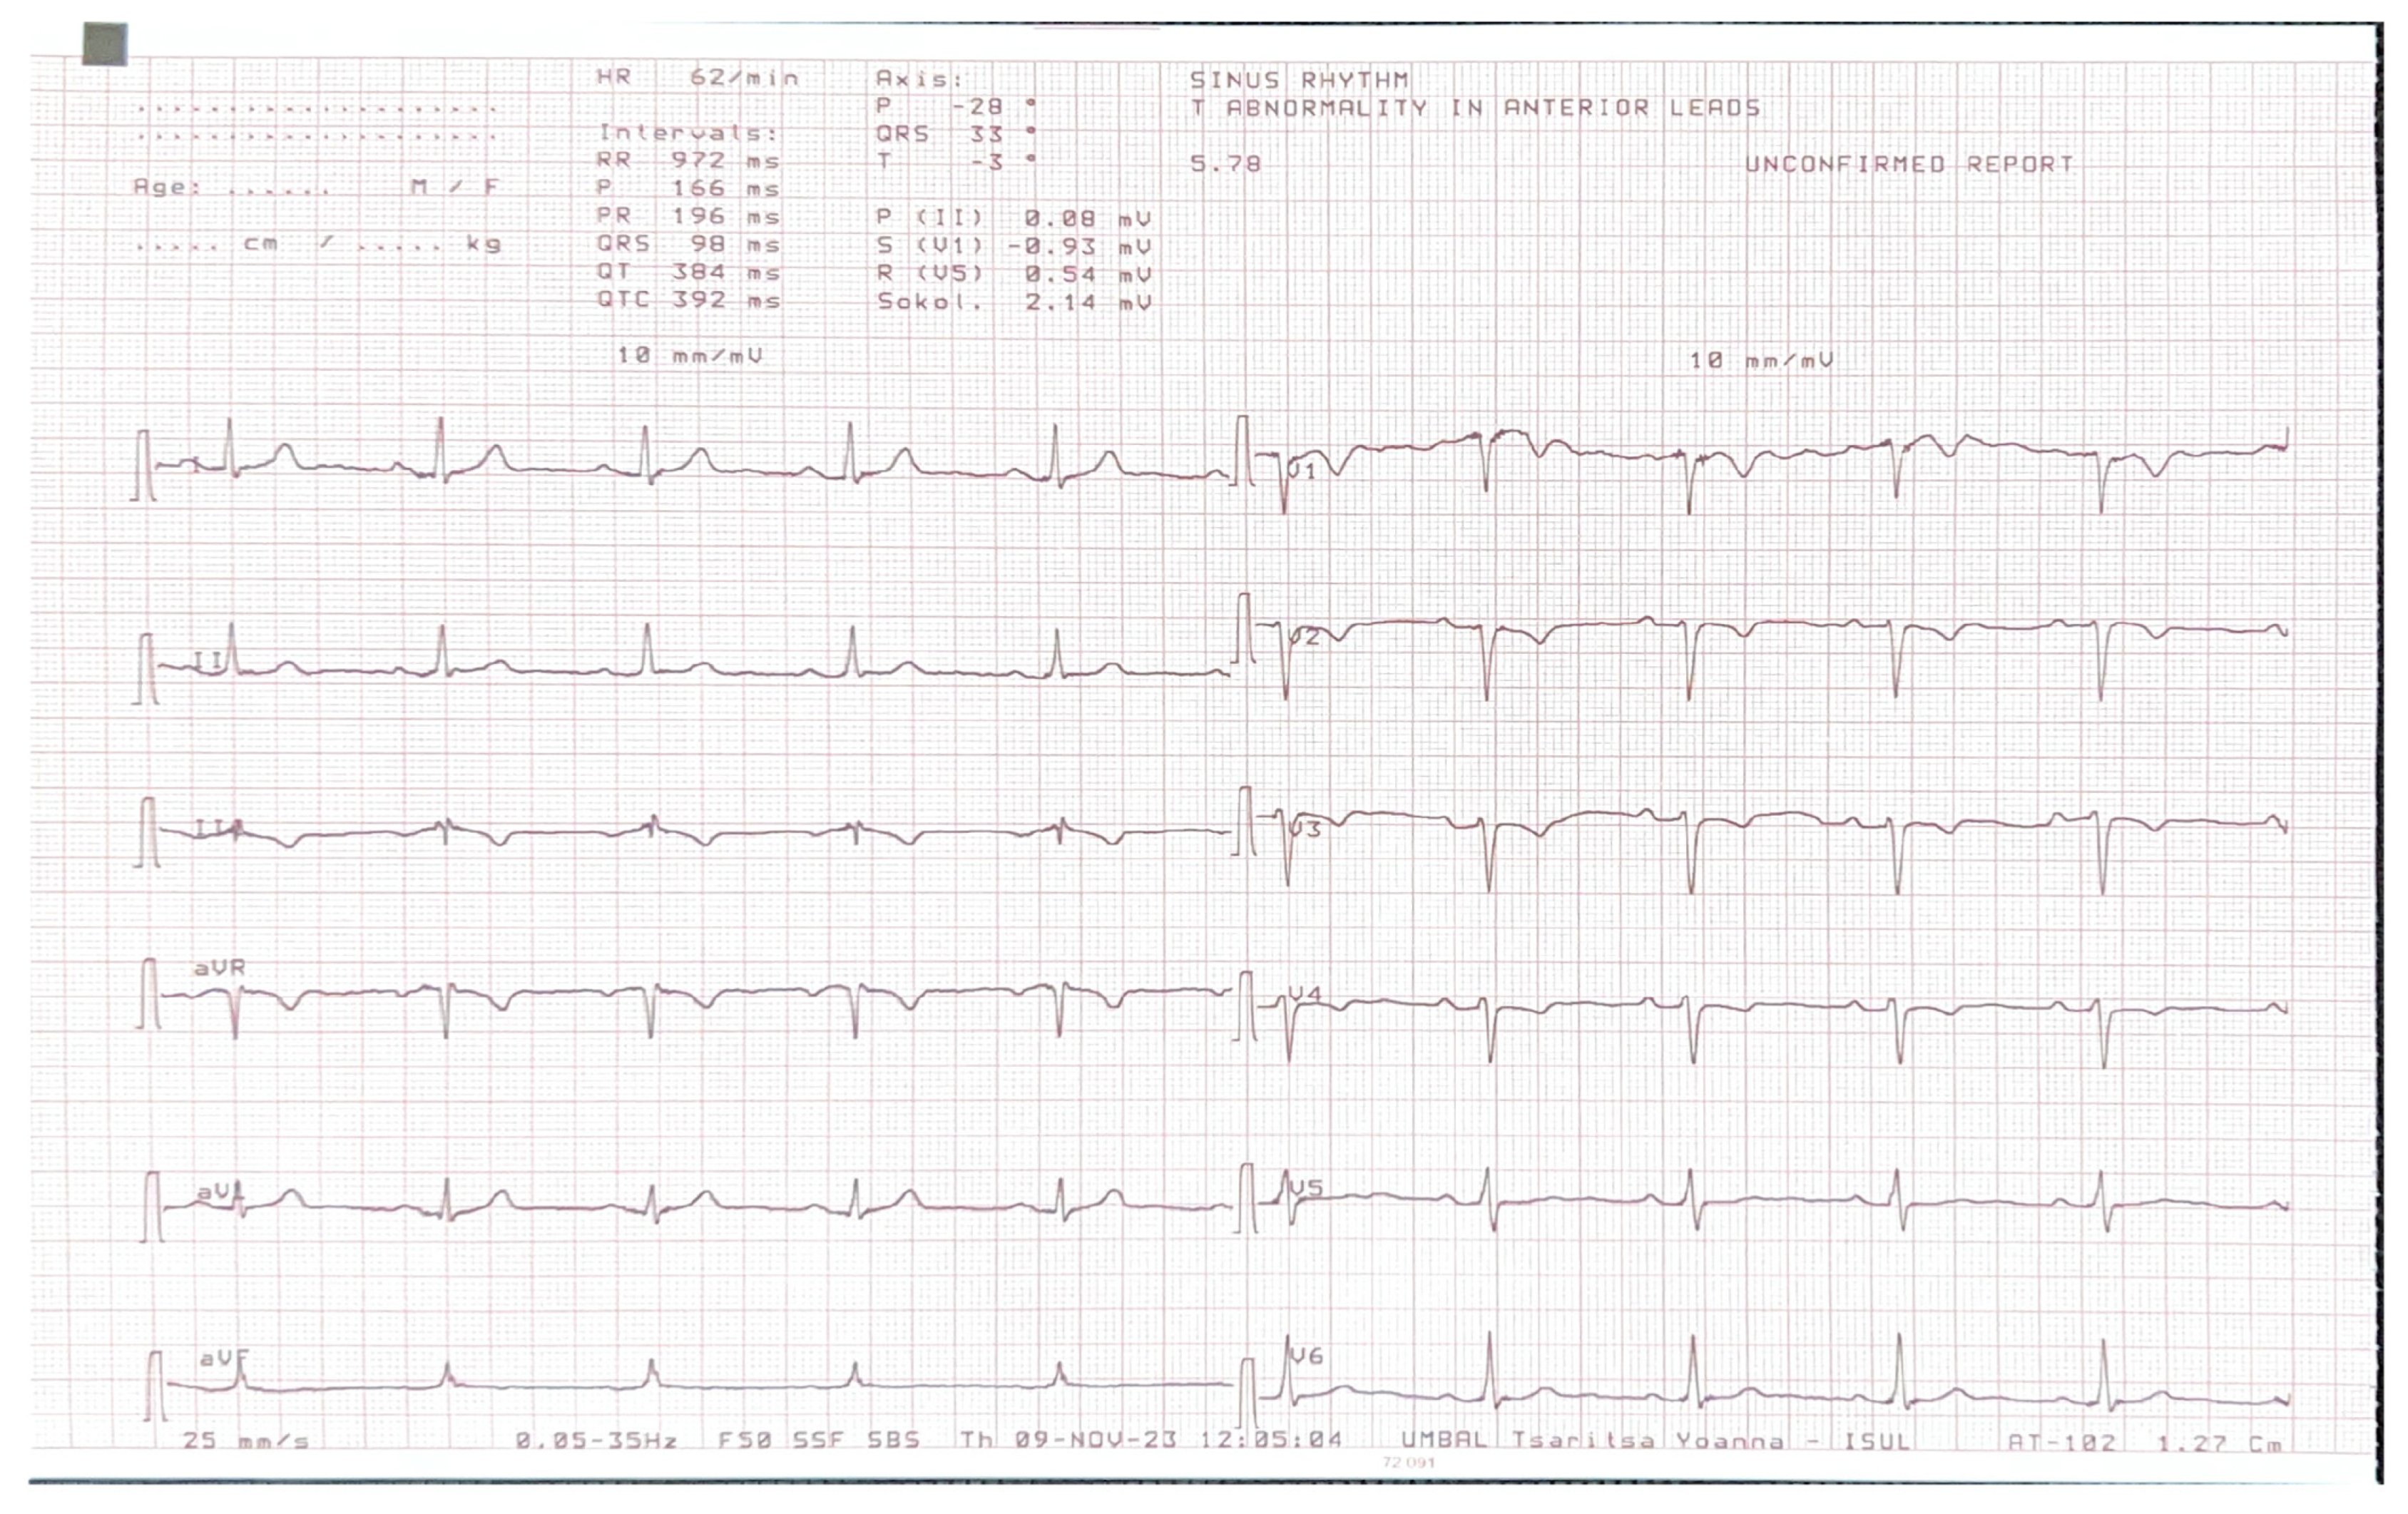

On 2D transthoracic echocardiography (TTE), an unusual heart position was noted with poor image quality from the standard acoustic windows. The parasternal long axis view gave the impression of right ventricular dilatation. An exaggerated motion of the left ventricular posterior wall was noted with hyperechogenic space behind it, which initially has been thought to be pericardium. The left ventricular apex was displaced laterally and posteriorly and was impossible to be visualized from the standard apical views (Figure 2). The apex was better demonstrated when the patient was not in left lateral but in supine position. The findings raised the suspicion of the atrial septal defect, and the patient was referred for CMR for further evaluation.

Figure 2. Two-dimensional transthoracic echocardiography. (A)—Parasternal long axis view gave the impression of right ventricular dilatation. Hyperechogenic space behind left ventricular posterior wall. Poor image quality. (B)—It was impossible to visualize the apex of the heart from the standard apical views in left lateral position.